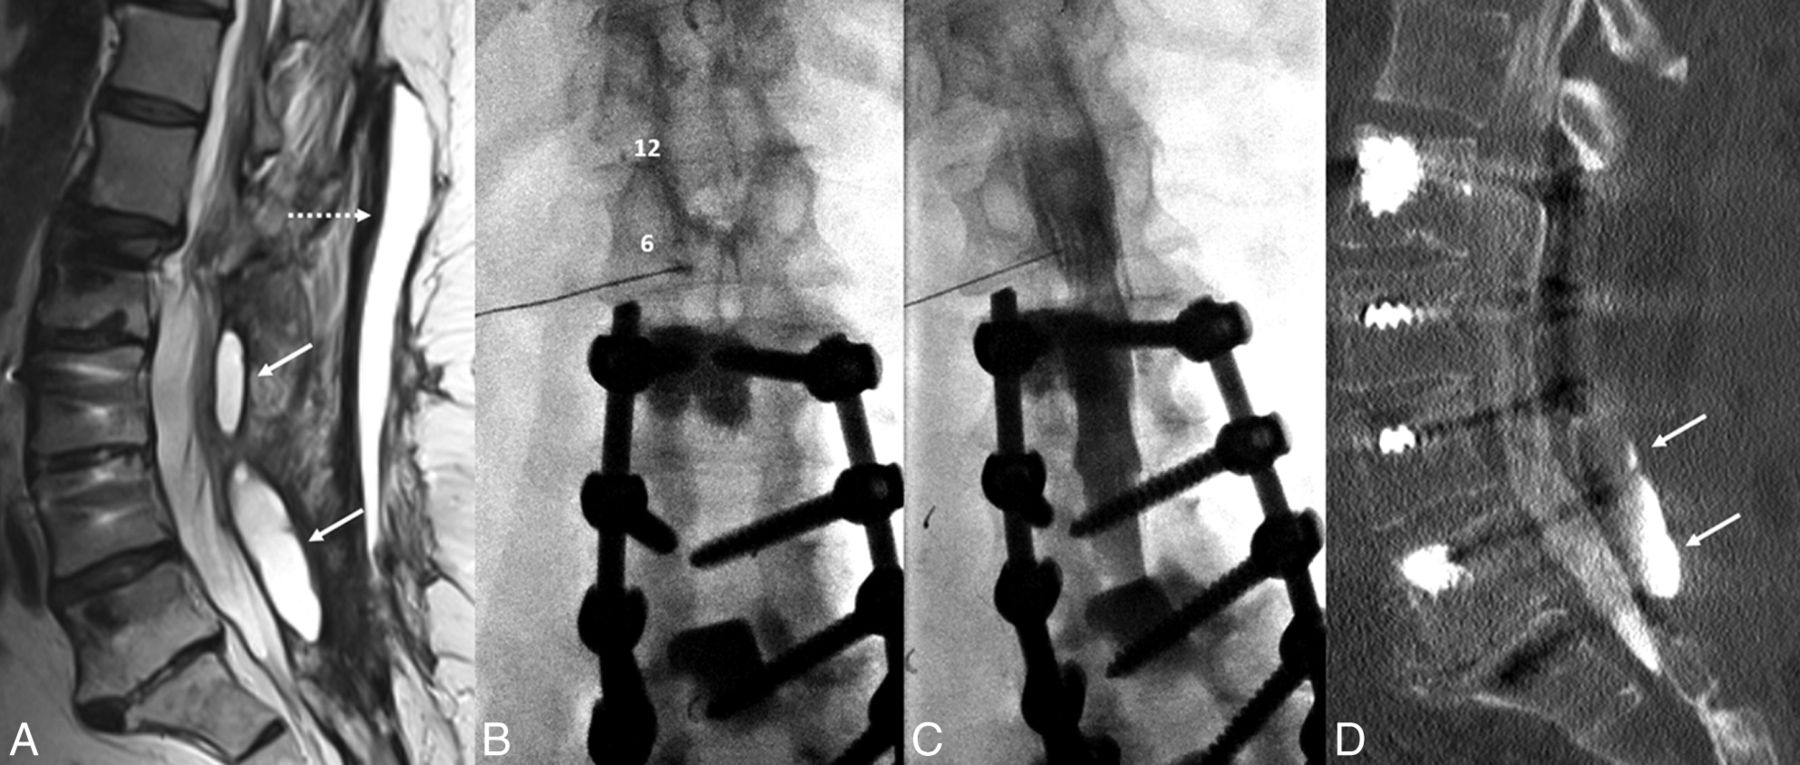

A 67-year-old woman with a history of multiple previous spinal fusion procedures presented with newly worsening low back and radicular leg pain 6 months after lumbar fusion and laminectomy. Spine MRI showed 2 paraspinous fluid collections and a large midline subcutaneous fluid collection, all of which exhibited rim enhancement (Fig 1). With clinical suspicion of abscess versus pseudomeningocele communicating with the CSF, percutaneous aspiration of the fluid collections and CT myelography were requested to determine the etiology of the pain and evaluate the provisional diagnosis of pseudomeningocele. Both procedures were scheduled on the same day at the request of the ordering surgeon, given the patient's social and transportation difficulties.

A 67-year-old woman with a history of multiple spinal fusions presented with newly worsening low back and radicular leg pain (case 1). Sagittal T2-weighted MR imaging (A) shows 2 paraspinous fluid collections (white arrows) within the deep paraspinal musculature and a midline subcutaneous fluid collection (dashed arrow) with rim enhancement on postcontrast series (not shown). B, Anteroposterior fluoroscopy image of myelography with TFLP. The needle tip is beyond the medial edge of the pedicle at the 5 o'clock position (relative to the pedicle). Note the position of the needle inferior to the expected location of the exiting nerve root and dorsal root ganglion. C, Oblique fluoroscopy image shows contrast extending into the intrathecal space after injection through the left L1–2 foramen. D, CT myelogram demonstrates the inferiorly located cystic collection filled with contrast, confirming a pseudomeningocele (arrows).

The patient was placed in a prone position under moderate sedation. The initial intent was to drain enough of the midline fluid to allow a steep oblique interlaminar approach for myelography using a combination of fluoroscopy and sonography. After 46 mL of fluid was drained, sonography showed residual fluid that, if traversed, could potentially contaminate the intrathecal compartment. Despite sedation, the patient was too agitated to safely undergo a C1–2 puncture, and rescheduling with the patient under general anesthesia was not desirable. As the back was already exposed and appropriately positioned, we elected to attempt TFLP. After re-prepping, a 5-inch 22-ga spinal needle was used to puncture the thecal sac at a 35° oblique transforaminal, infraneural approach at the L1–2 level using C-arm fluoroscopy, more oblique than usual for a transforaminal epidural injection (Fig 1). This approach was selected to minimize the risk of injury to the dorsal root ganglion, guiding the needle posterior and inferior to the known location of the ganglion seen by previous MR imaging and inferior to the conus medullaris. The patient tolerated the procedure well without any immediate complication.